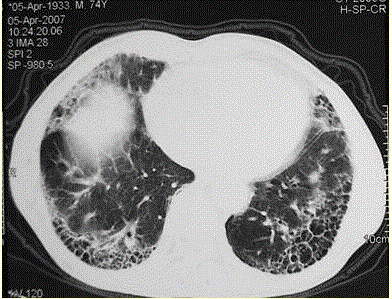

问题  患者男,73岁。进行性呼吸困难半年,加重2个月。否认吸烟史、粉尘接触史。查体:发绀,杵状指,双肺底闻爆裂音。血常规正常,ERS 16 mm/h。胸部CT 如图所示。 最可能的诊断是

选项 A、支气管扩张症 B、NSIP C、UIP D、肺部感染 E、COPD

答案 C